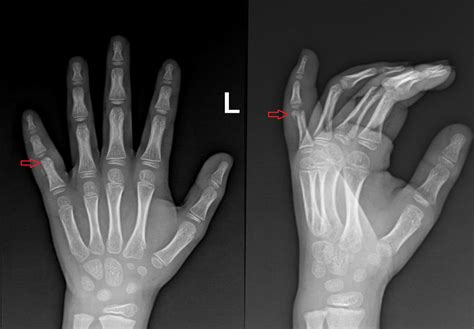

- Röntgenové lúče: V mnohých prípadoch veterinárny lekár urobí röntgenové snímky poraneného prsta, aby získal detailný pohľad na kosti a potvrdil prítomnosť a závažnosť zlomeniny.

Základom diagnostiky zlomeniny prsta je RTG vyšetrenie.

Na základe zistení z vyšetrenia a röntgenových snímok bude vedieť veterinár určiť presnú lokalizáciu a typ zlomeniny, čím nasmeruje vhodný plán liečby.